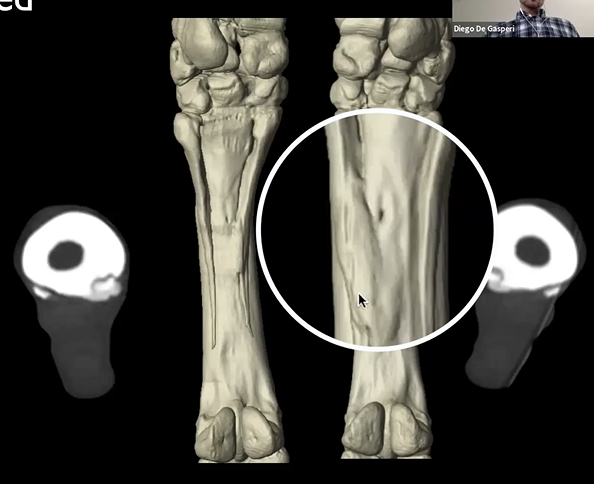

Read MoreThis horse came in for a suspected splint bone fracture. CT images show new bone formation involving the axial aspect of both medial splint bones. Featured: Dr. Diego De Gasperi, University of Wisconsin-Madison